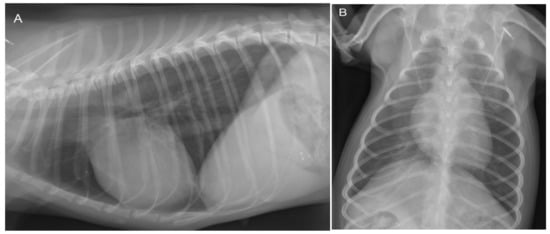

Because of the history of respiratory distress, thoracic radiographs were made, which revealed no abnormalities (Figure 2).

Figure 2. Lateral (A) and dorso-ventral (B) thoracic radiographs show no abnormalities at 3 years of age. The cardiac silhouette has a normal size and shape in both projections. The vertebral heart scale (VHS) is 10.5, which is within the breed-specific reference range for chihuahuas (8.9–11.0) [14]. There are no changes in the pulmonary parenchyma and pulmonary vasculature visible.

Because DCRV is a rare condition, there are only a few papers that report on the associated clinical signs [9,10,11,12]. Clinical presentation in dogs and humans is very similar and can range from lack of clinical signs through dyspnea on exertion to congestive right-sided heart failure [7,8,9,10,11,12]. Most clinical signs reported in dogs are either exercise intolerance with or without syncope because of low cardiac output secondary to the right ventricular obstruction or signs of congestive right-sided heart failure [9,10,11,12]. Because the reported pressure gradients caused by the DCRV both in dogs and humans are typically less than 80 mmHg, the right ventricular systolic pressure rarely exceeds left ventricular systolic pressure [7,8,9,10,11,12]. Flow-direction through the VSD in these cases is left-to-right [7,8,9,10,11,12]. In the present case, at 10 weeks of age, the right ventricular obstruction was only mild, which allowed left-to-right shunting via the VSD. However, this high-velocity turbulent jet resulted in structural changes in the right ventricle that led to a roughly 60 mmHg increase in the right ventricular obstruction in 3 years, resulting in a supra-systemic right ventricular systolic pressure and, in turn, a flow-reversal via the VSD. The leading clinical sign in the presented dog was exertional dyspnea, most likely attributable to systemic hypoxemia due to the shunting of deoxygenated blood from the right ventricle to the left ventricle through the VSD [1,2,3,9]. The initial diagnostic test of choice in a dog presenting with dyspnea without noisy breathing is usually thoracic radiography. In the present case, no radiographic abnormalities were seen in the thorax, which finding made most pulmonary parenchymal pathologies, including cardiogenic pulmonary edema, as the cause of dyspnea very unlikely. The cardiac silhouette was normal in size. Concentric right ventricular hypertrophy would not result in cardiac chamber enlargement, especially when the left ventricle is underfilled. As a result, radiographic cardiomegaly is unlikely, similar to cases of severe pulmonic stenosis. Echocardiography with a bubble-study confirmed intra-cardiac right-to-left shunting as the most likely cause of the leading clinical signs. Arterial blood gas analysis was not performed because of difficulties obtaining an arterial blood sample in such a small dog. Exercise intolerance was most likely caused by insufficient tissue oxygenation due to impaired tissue perfusion caused by erythrocytosis and hypoxemia due to right-to-left intra-cardiac shunting. Both cerebral hypoxia and cerebral hypotension can lead to transient loss of consciousness, which was considered the most likely reason for the syncopal episodes in this dog.